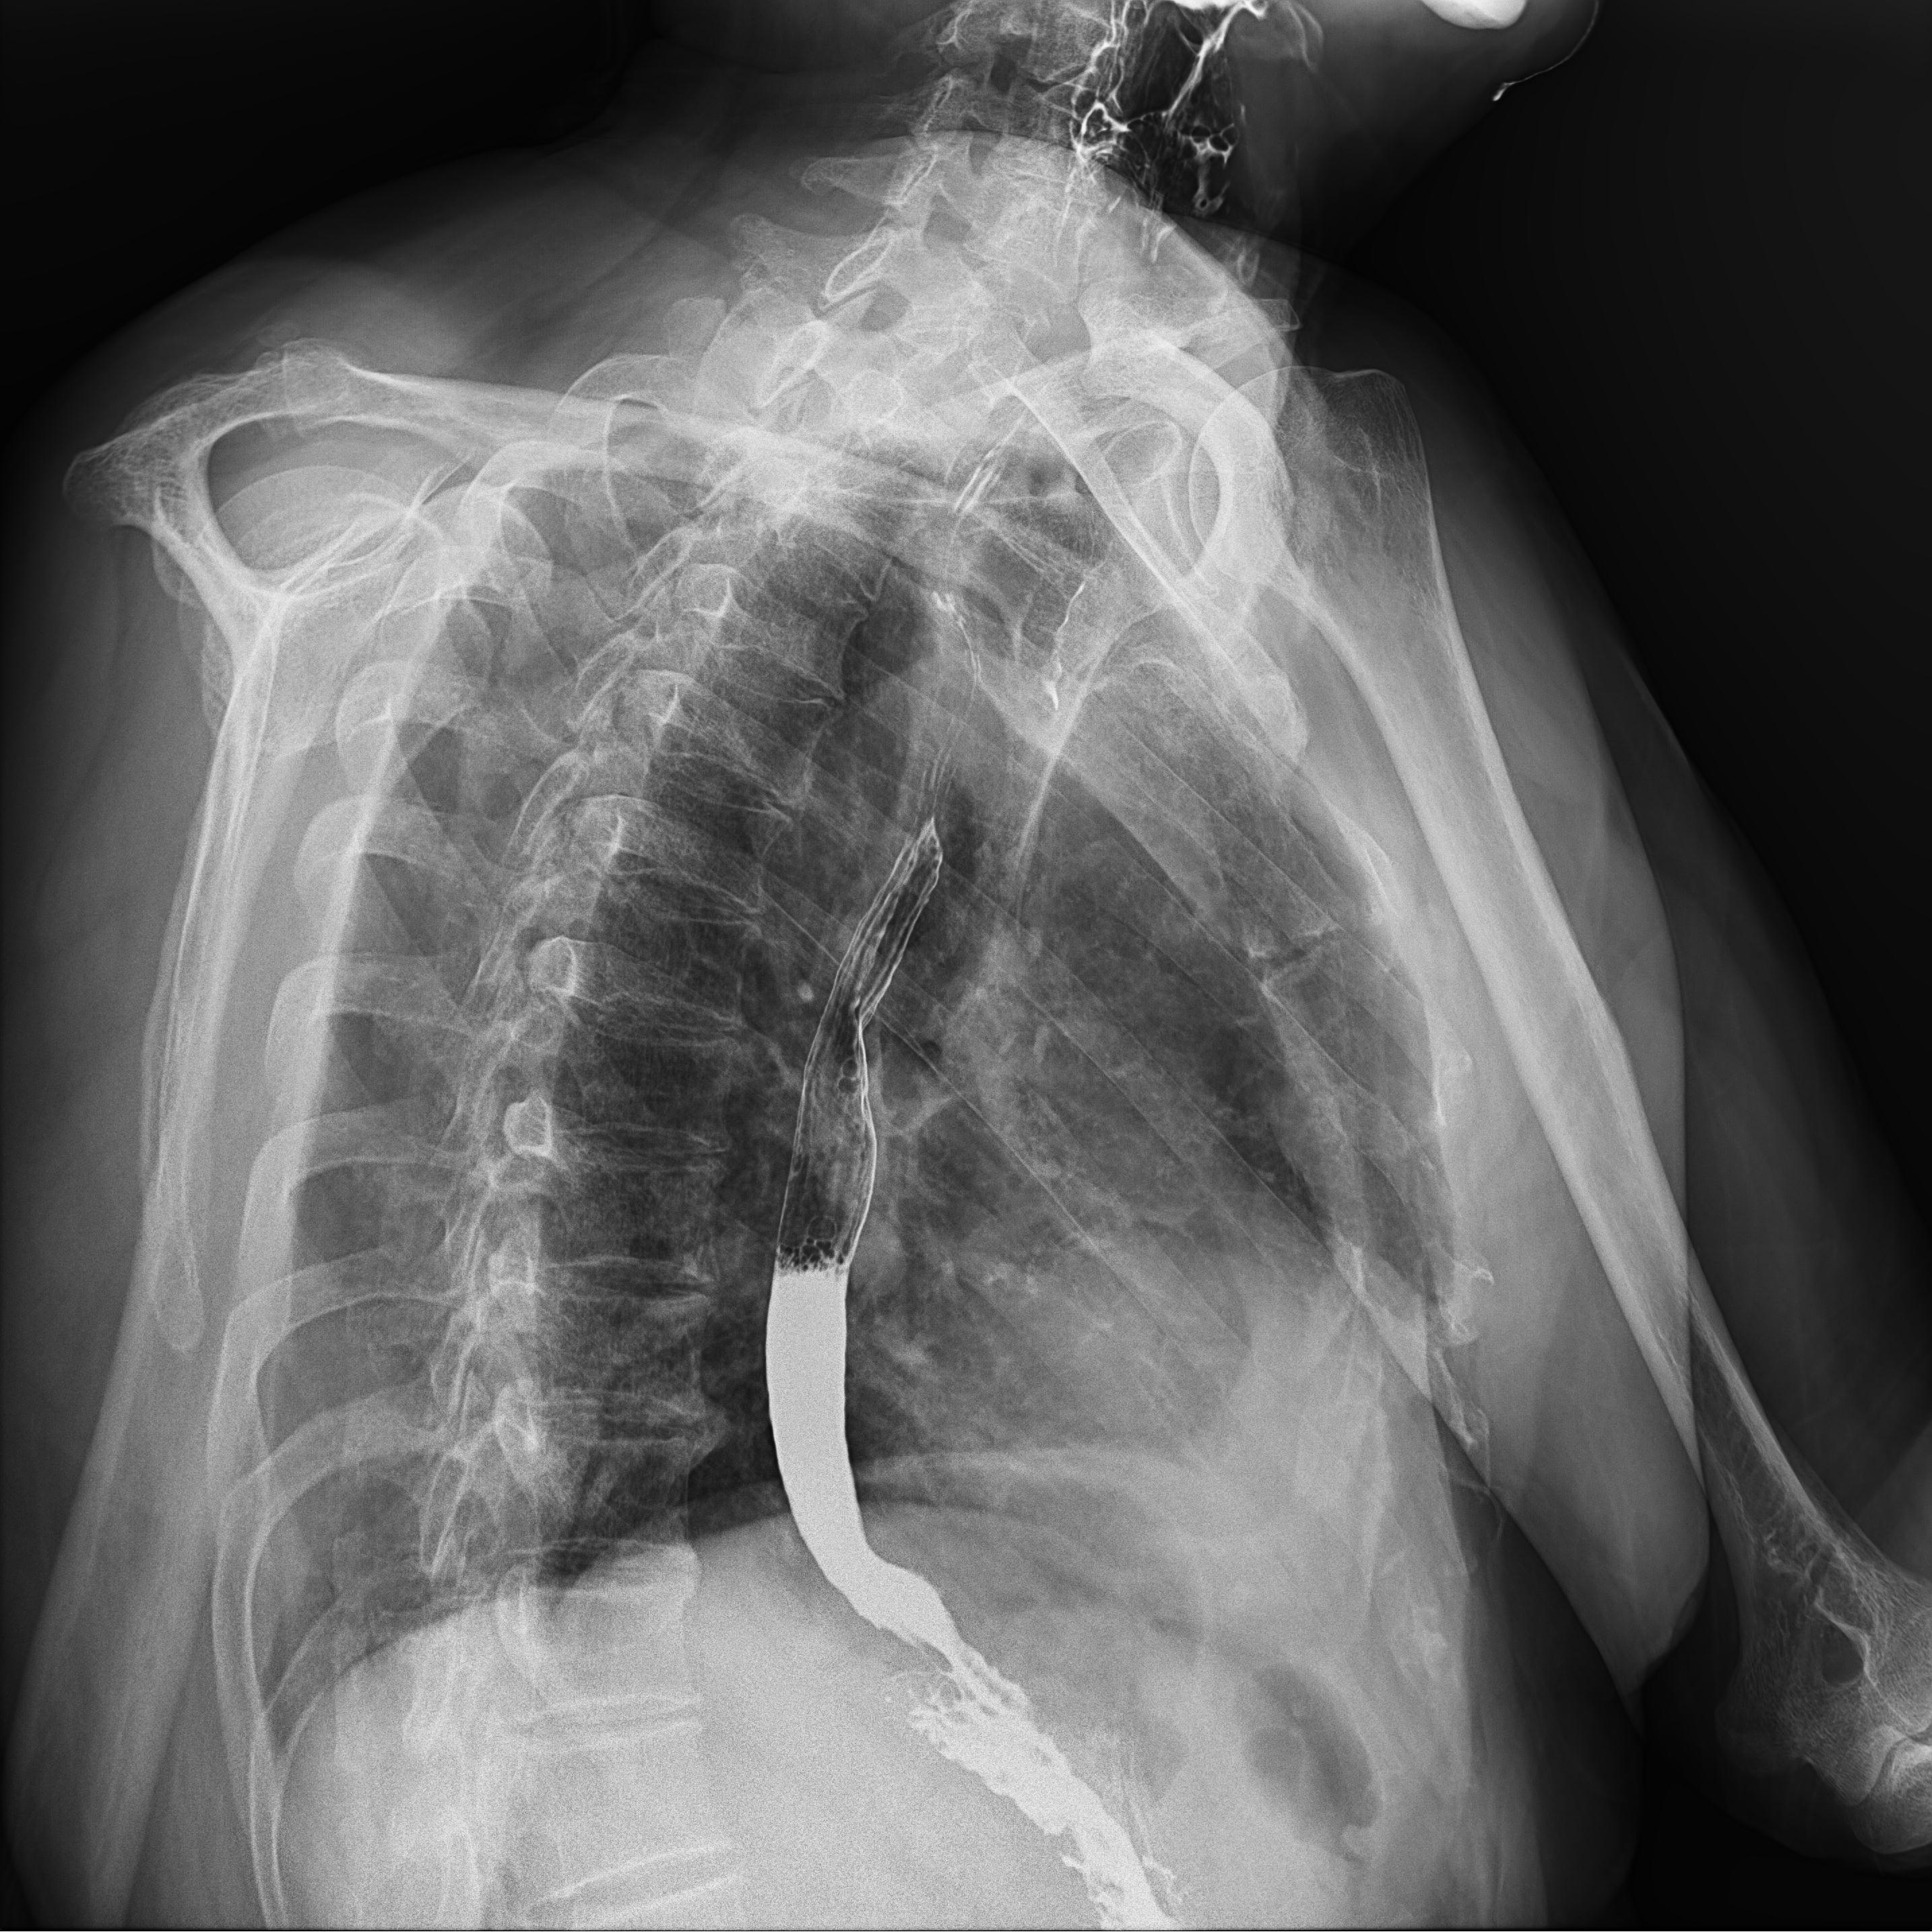

高千伏攝影